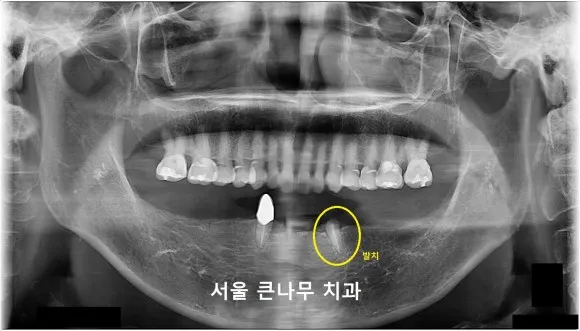

서울큰나무치과에 내원하셨던 67세 여성분 사례입니다.

이 환자분의 경우, 위턱의 경우 치료한 치아도 많이 없고 연세에 비해 건강한 것에 비해 아래턱은 단 두 개의 치아에 의존하여 틀니를 사용하고 계셨고 그마저도 이가 부러짐에 따라 기존 틀니를 사용할 수 없게 되었습니다.

65세 이상은 보험 임플란트 2개가 적용되기에 임플란트 총 3개를 식립하였지만 2개의 보험 적용으로 경제적인 부담을 많이 줄일 수 있었습니다.